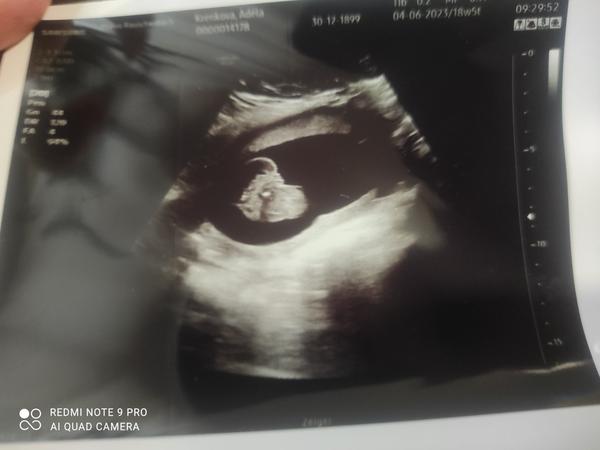

Je to holka nebo kluk? Nejistota po vyšetření ultrazvukem.

ahoj holky co vidíte jsem v 20 tt. v 16 týdnů mi můj gynekolog rekl vidí na 85 procent kluka a dnes gynekolozka řekla ze vidí zase holku dneska to je 20 týden

@baby03 tak za mě je tohle tedy utz snímek holčičky 🙂

Kluci to mají spise jako doslova mezi nozickama tohle mi přijde jako přímo v rozkroku, u syna jsem měla pindika na fotce a byly tam stehynka uprostřed pindik mezi stehýnkama a tam kousek odd prdelky měl koulicky takže tohle spis holka